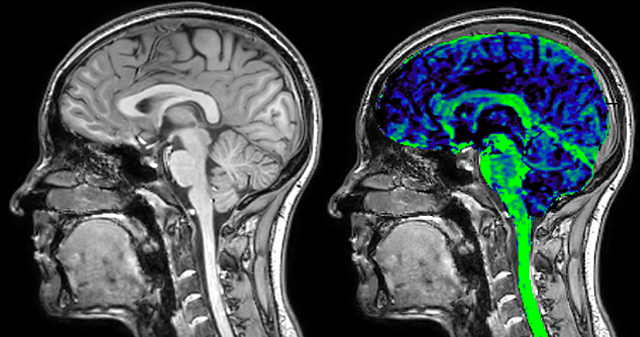

T1 - weighted

Myelin water imaging (echo 1)

T1 - Weighted, Myelin Water Fraction Superimposed

Spinal cord coverage

Smaller, more isotropic voxels

Excellent detail in quantitative maps

Images courtesy of Adam Dvorak, Department of Physics and Astronomy, University of British Columbia